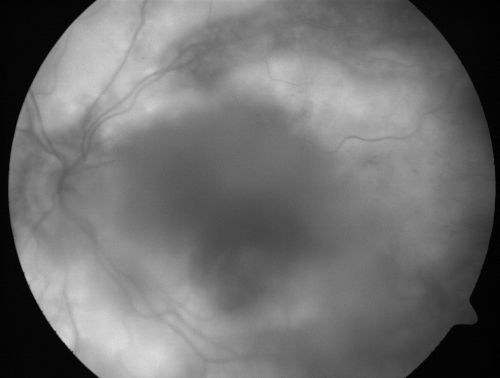

Progressive Outer Retinal Necrosis 77 Year Old Woman with CLL (Acute Retinal Necrosis) (PORN - ARN)

77-year-old woman with CLL who had shingles on the left side of her face about 6 weeks ago then she developed a dendrite in the cornea which was treating about four weeks ago.  She noticed severe vision loss in the left eye just a few days ago and you saw retinitis and she comes in because of that.   Vision OD is 20/25, OS is hand motion